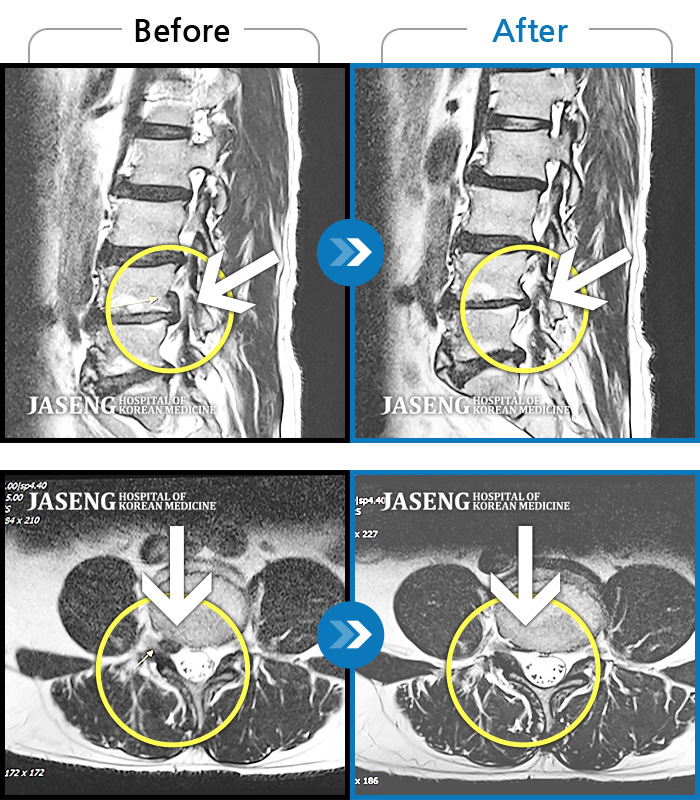

Before

After

환자에게 사전 동의를 받아 동일 조건에서 촬영되었습니다.

개인에 따라 치료 후 부작용이 발생할 수 있으니 의료진과 상담 후 치료를 진행하시기 바랍니다.